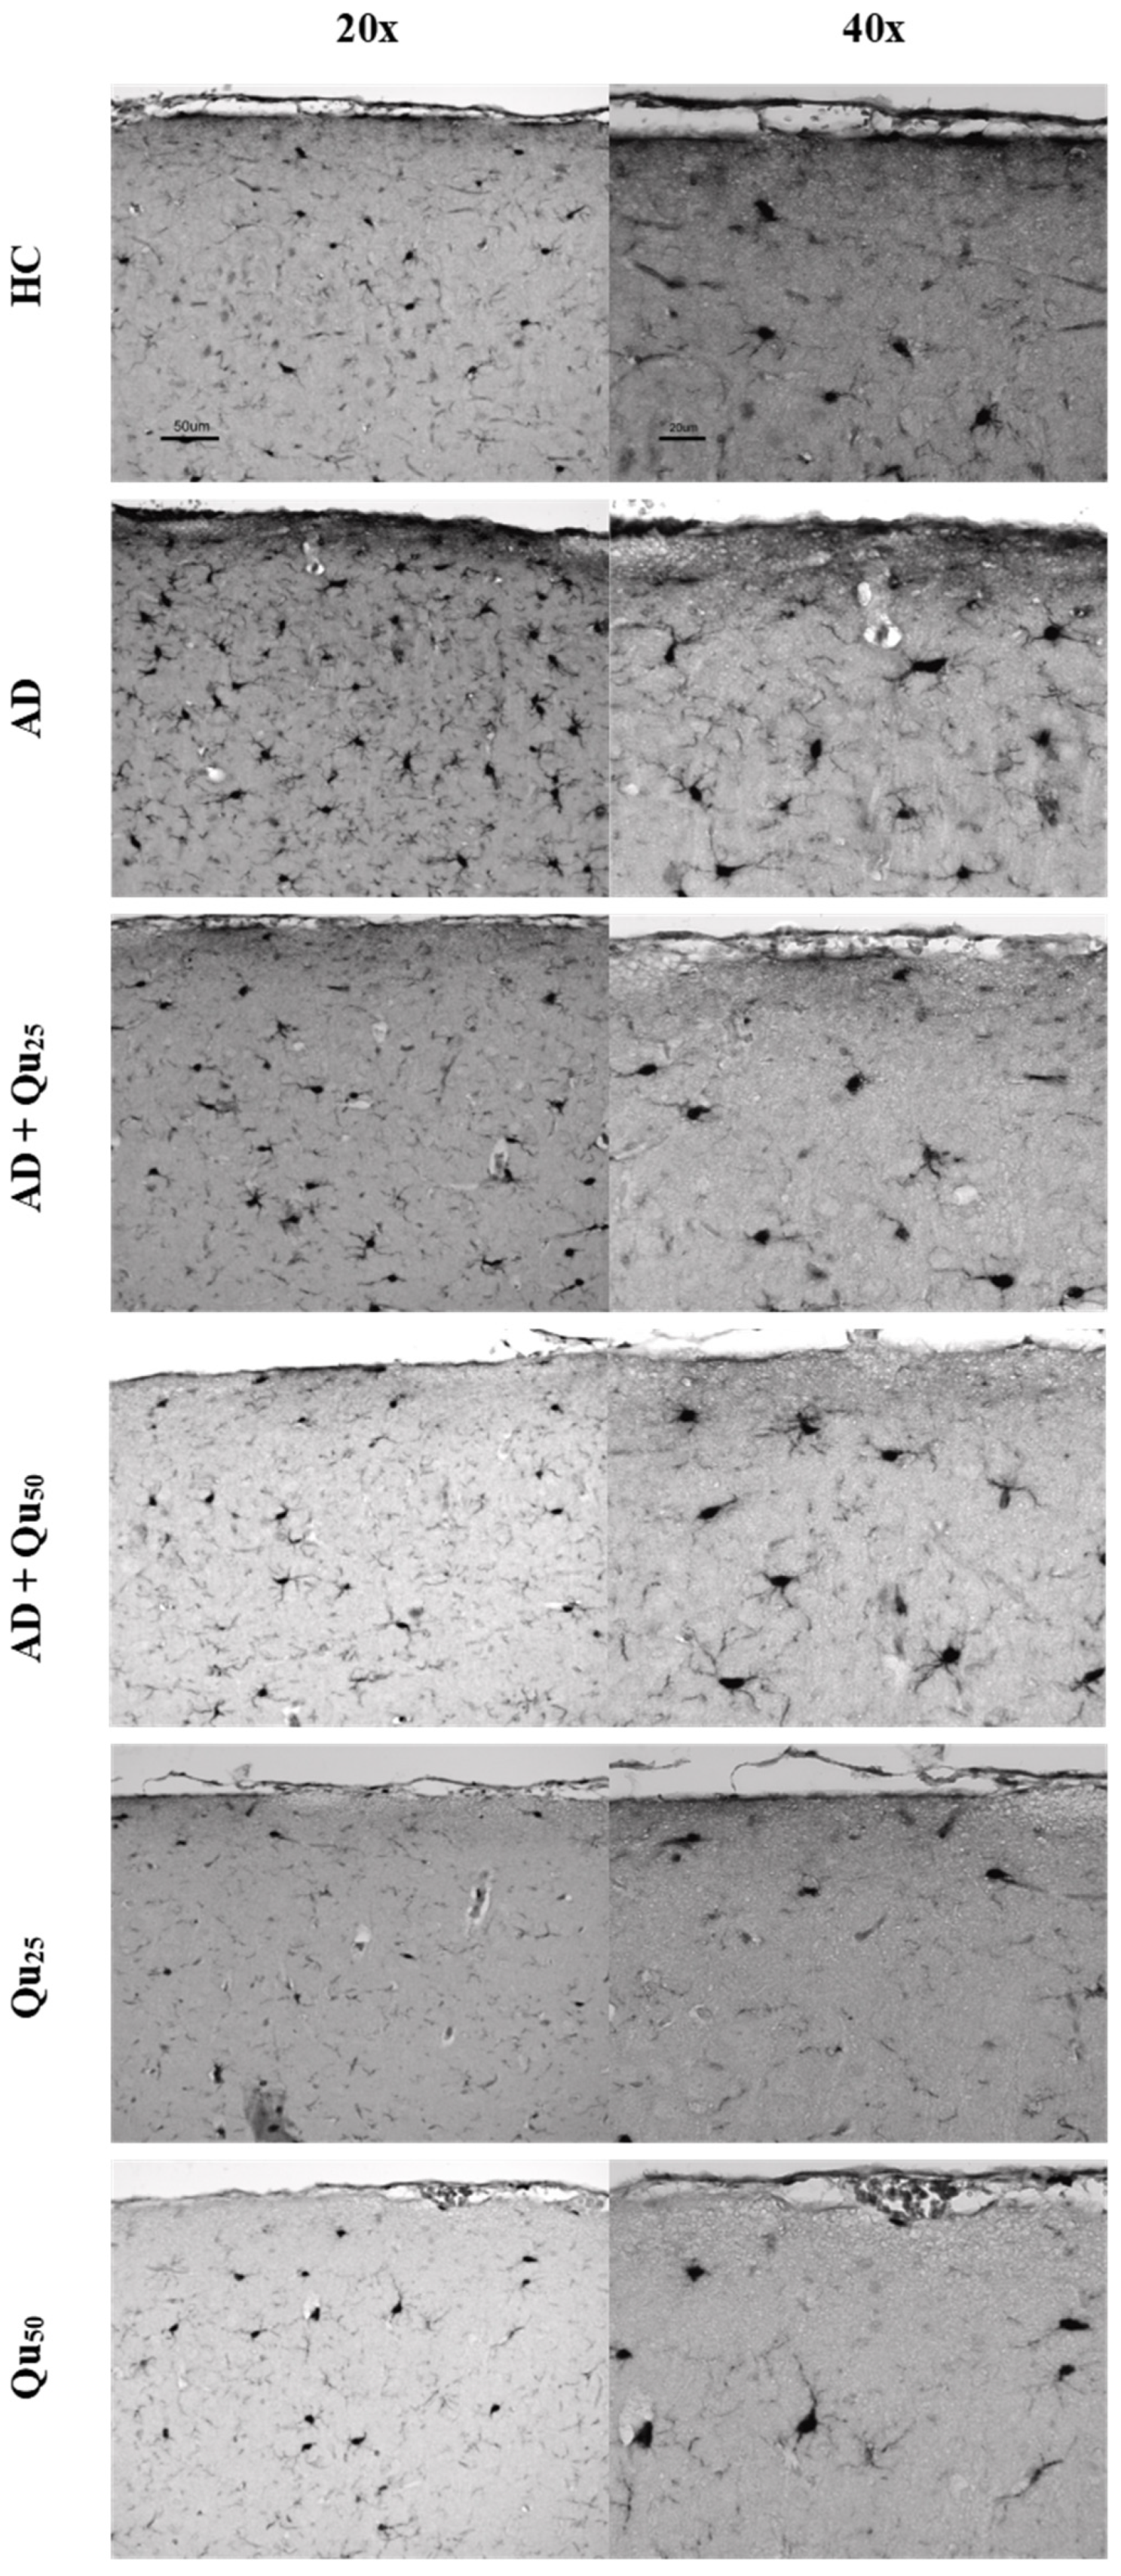

The Iba1 protein plays a crucial role in phagocytosis and membrane folding. This marker identifies microglial cells in both the resting phase and the initial phase of activation, and it clearly highlights the morphology of these cells, particularly the long-branched extensions. The expression of the Iba1 marker is shown in Figure 8 and Figure 9, as well as in Table 2.

A semiquantitative analysis of the microscopic images and quantitative data processing revealed that the expression of the Iba1 marker was significantly increased in the AD group in the cerebral cortex (Table 2) compared to the other treated groups (p = 0.0083). In hippocampal formation (Table 2), increased immunoreactivity was observed in the dentate gyrus (GD) of the AD and AD + Qu25 groups compared to the HC (p = 0.00013) and Qu50 (p = 0.0083) groups. Additionally, increased immunoreactivity was noted in the CA1 area of the HC, AD, and AD + Qu25 groups compared to the AD + Qu50, Qu25, and Qu50 groups (p = 0.0012). Finally, in the subiculum (SUB) area, increased immunoreactivity was observed in the HC and AD groups compared to the Qu25 and Qu50 groups (p = 0.00013).

HLA-DR, Iba1, and CD68 are widely used markers for characterizing different stages of microglial activation. According to Hendrickx et al. [38], HLA-DR and CD68 markers indicate immune activation and the response to tissue damage, while Iba1 is more suitable for structural studies in the absence of pathology. In our study, we detected only Iba1 in microglia located in areas with diffuse plaque formation (Figure 8 and Figure 9, Table 2). These results suggest that Iba1 may serve as an early activation marker of microglia, while HLA-DR and CD68 appear more strongly associated with dense-core senile plaques. These findings are consistent with the neurological screening data (Table 4).